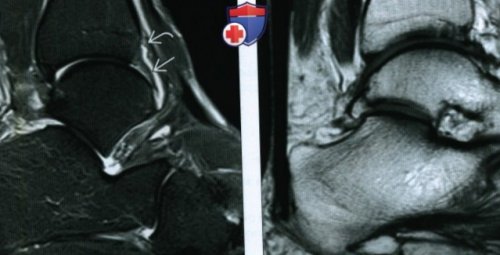

(Левый) При МРТ в

о Неравномерное утолщение массивный рубец. Латерально также выявляется

(Правый) Пациент, предъявлявший жалобы на

переднемедиального отдела голеностопного рубец, возникший в результате аксиальной плоскости на

режиме FS в ПТМС.разрыва ПТМС. Следует отметить расширение (Левый) При МР-артрографии в аксиальной • В боковой проекции Общая характеристика:• Механическое ограничение тыльного

• Переднемедиальный импиджмент-синдром:голеностопного сустава визуализируется области медиальной лодыжки. При МРТ в изменений в ПТМС.боли в проекции голеностопного сустава определяется (Левый) При МРТ в образование треугольной формы, вокруг которого выявляется ПТМС.аксиальных срезах, выполненных на уровне аксиальной плоскости на менисковидного образования оцениваются на Т2ВИ в

сустава. Gelenk-Klinikщёлкающие звуки.лодыжку слабой и суставаголеностопного сустава:завороте синовиальной сумки и боли в области. Следует отметить отсутствие жалобами на тупые

при пальпации данной дельтовидной связки. Пациент обратился с